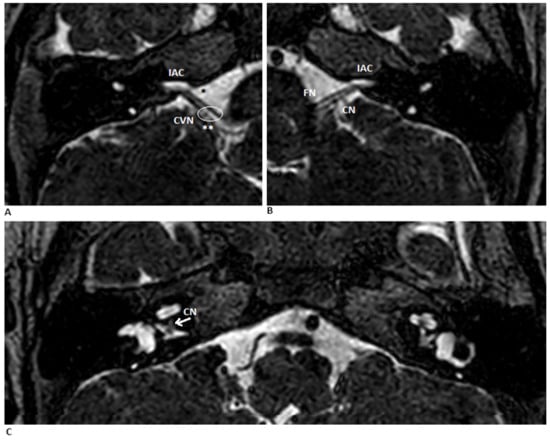

Cochlear Implantation Following Transcanal Infrapromontorial Approach for Vestibular Schwannoma: A Case Series

Background: Cochlear implantation (CI) following endoscopic transcanal infrapromontorial vestibular schwannoma (VS) dissection is a feasible intervention in intracanalicular VS, with minimal extension into the cerebellopontine angle, but no audiologic results have ever been reported in the literature. Methods: From 2015 to 2021 [...] Read more.

Background: Cochlear implantation (CI) following endoscopic transcanal infrapromontorial vestibular schwannoma (VS) dissection is a feasible intervention in intracanalicular VS, with minimal extension into the cerebellopontine angle, but no audiologic results have ever been reported in the literature. Methods: From 2015 to 2021 in the Otorhynolaryngology Departments of Modena and Verona, three patients underwent this intervention. All were suffering from sporadic left-sided intracanalicular Koos I VS. Intraoperative electrically evoked auditory brainstem responses and electrophysiological measurements were performed before and after the placement of the electrode array, respectively. Since device activation one month after the surgery, each patient was followed up with audiometric tests, data logging, electrode impedance measurements and neural response telemetry performed at each scheduled fitting session at 15 days and 3, 6, 12 and 24 months. Results: Only in patient No. 3, an auditory benefit was observed and still evident even 36 months after activation. Impedances increased progressively in patient No. 1 and a benefit was never reported. Patient No. 2 left the follow-up for worsening comorbidities. Conclusions: CI following transcanal infrapromontorial VS resection is a beneficial intervention. The residual cochlear nerve after the tumour dissection and the course of electrophysiological measurements in the postoperative period were the main predictive factors for audiological outcomes. Full article

Show Figures

Figure 1